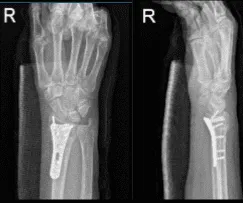

C-arm images were taken and manipulated to be in the correct position. Finding The plate in appropriate position, fixation of the distal radius performed using locking and nonlocking screws distally and proximally.

Final images were taken and saved. The wound was washed. Closure of the wound was done in layers. Marcaine 0.5%, 6 cc were used for locales. The skin was closed with Monocryl #4-0. A short-arm splint was applied. Shoulder sling was given. The patient was extubated and moved to the postoperative care unit in a stable condition.

After two weeks, the patient checked in with a presented Xray and saw that osseous and metallic elements are in good alignment. Patient is still in splint but not taking any pain medications. In 4th week’s post operation, observed plate fixing the distal radius is again noted with screws holding the plate in good position.

AP and Lateral View of Patient RT 2 weeks Post-operative

AP and Lateral View of patient RT wrist 2 weeks Post-operative